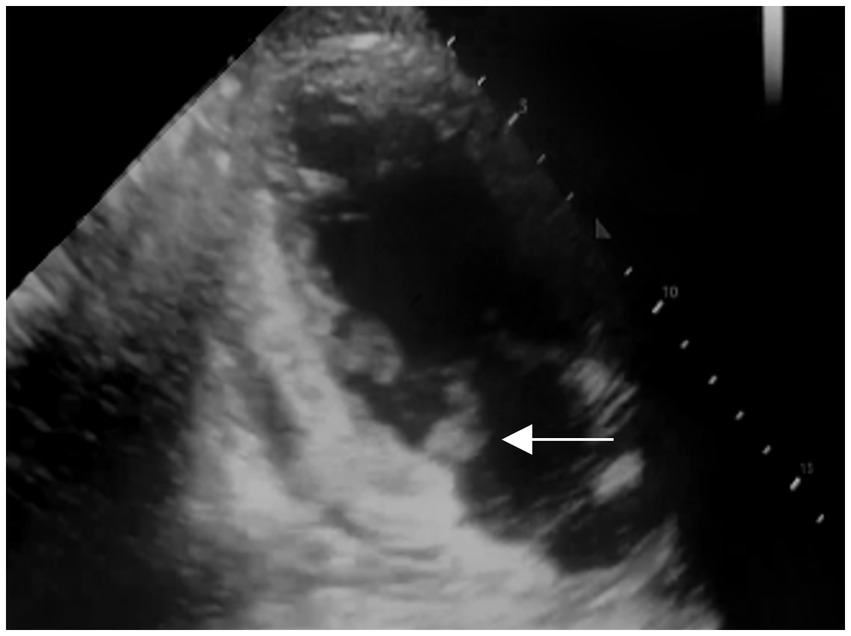

After admission, he received treatment, including rehydration, vasopressor (metaraminol bitartrate), antibiotics (imipenem-cilastatin sodium and moxifloxacin), prednisone (5 mg qd), and other support treatment. Pathogens were negative after 7 days of blood culture. On day 7 of treatment, the patient had a sudden convulsion with repetitive jerks, loss of consciousness, and eyes gazing to the right. A measure of 3 mg midazolam was injected to control symptoms, and cranial CT (Figure 3) was performed again, which revealed multiple low-density regions of both the cerebral and cerebellar hemispheres. Patent foramen ovale (PFO) was negative on transthoracic and contrast echocardiography, but it showed 0.7 cm*0.6 cm vegetation on the mitral valves (Figure 4, white arrow). Up to this point, infectious endocarditis was diagnosed.

Figure 4

Transthoracic and contrast echocardiography of the patient 7 days after the first echocardiography (white arrow: mitral valve vegetation).

This patient presented with septic shock and tenderness of the lower limbs during the first consultation. IE is an important differential diagnosis; however, no significant findings were reported on the first echocardiography. After the sudden convulsion, mitral valve vegetation was detected by repeated echocardiography (7 days after the initial transthoracic echocardiography), with IE being a suspected cause of cerebral infarctions. Bacteremia is essential in the diagnosis of IE (2), and in this case, pneumonia and erysipelas are both important factors for disease progression. However, due to the early use of antibiotics before admission, the blood culture was negative. However, with one major criterion and three minor criteria met according to the modified Duke criteria (6), the diagnosis of IE remained valid. The complaint of blurred vision might have been an early signal of embolism shedding from mitral valve vegetation.